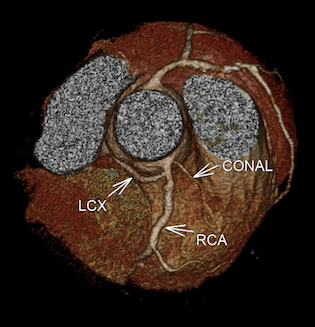

CASE 1- Coronary anomaly- LCX FROM RCA

Anomalous origin of the Left Circumflex artery from Right Coronary artery identified by imaging with Multidetector Computed Tomography

On MDCT angiography, left coronary artery was seen to arise from the left sinus of valsalva which further coursed along the anterior interventricular groove as LAD. RCA was seen to be arising from anterior aortic sinus with its normal course along right atrio-ventricular (AV) groove. There was a vessel seen arising form its proximal segment which took a retro-aortic course towards the left AV groove. It was labelled as LCX as it followed the normal course of the LCX along left AV groove.

Anomalous origins of the coronary artery are rare, but they are of paramount importance for their catastrophic sequelae like myocardial ischemia or even sudden death. MDCT has made it so easy for the detection of such anomalies due to its spatial resolution and 3D image reconstructionThough this anomaly is non-contributory to myocardial ischemia, it seems to be important to identify it as otherwise it would have been misdiagnosed as complete occlusion of LCX which was not the case.